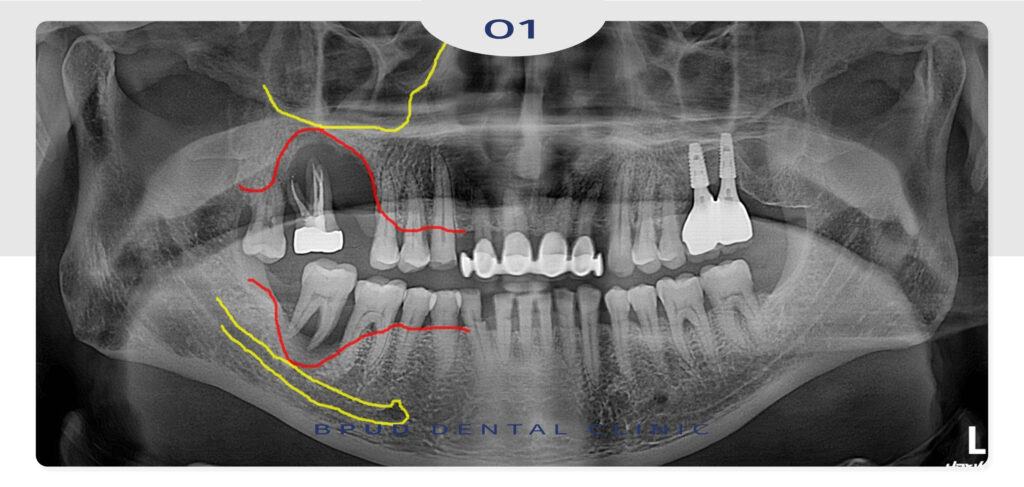

먼저 위, 아래 심한 염증이 진행되고 있는

원인 치아들을 발치하고 위쪽은 상악동 거상술,

아래쪽에는 뼈이식을 통해 임플란트 식립을

진행하는 것으로 계획을 수립하였습니다.

많은 양의 뼈이식을 동반한 임플란트

식립을 마친 모습입니다.

일반적인 뼈이식은 임플란트 식립 부위의

뼈 두께나 높이가 부족할 때 인공뼈 등을

보충해주는 치료로 주로 아래턱이나

위턱 앞니 등 상악동과 거리가 있는 부위에

시행하게 됩니다.

반면 상악동 거상술은 위턱 어금니 부위에만

적용되는 특수한 술식으로 위쪽 어금니 위에

있는 공간인 상악동에 뼈가 부족할 경우 그냥

뼈이식만 진행할 경우 임플란트가 상악동을

침범하거나 고정력이 떨어질 수 있어

상악동 내부의 얇은 막을 들어 올리는 거상술로

만들어진 공간에 뼈이식재를 채워 식립 환경을

만들어 주게 됩니다.